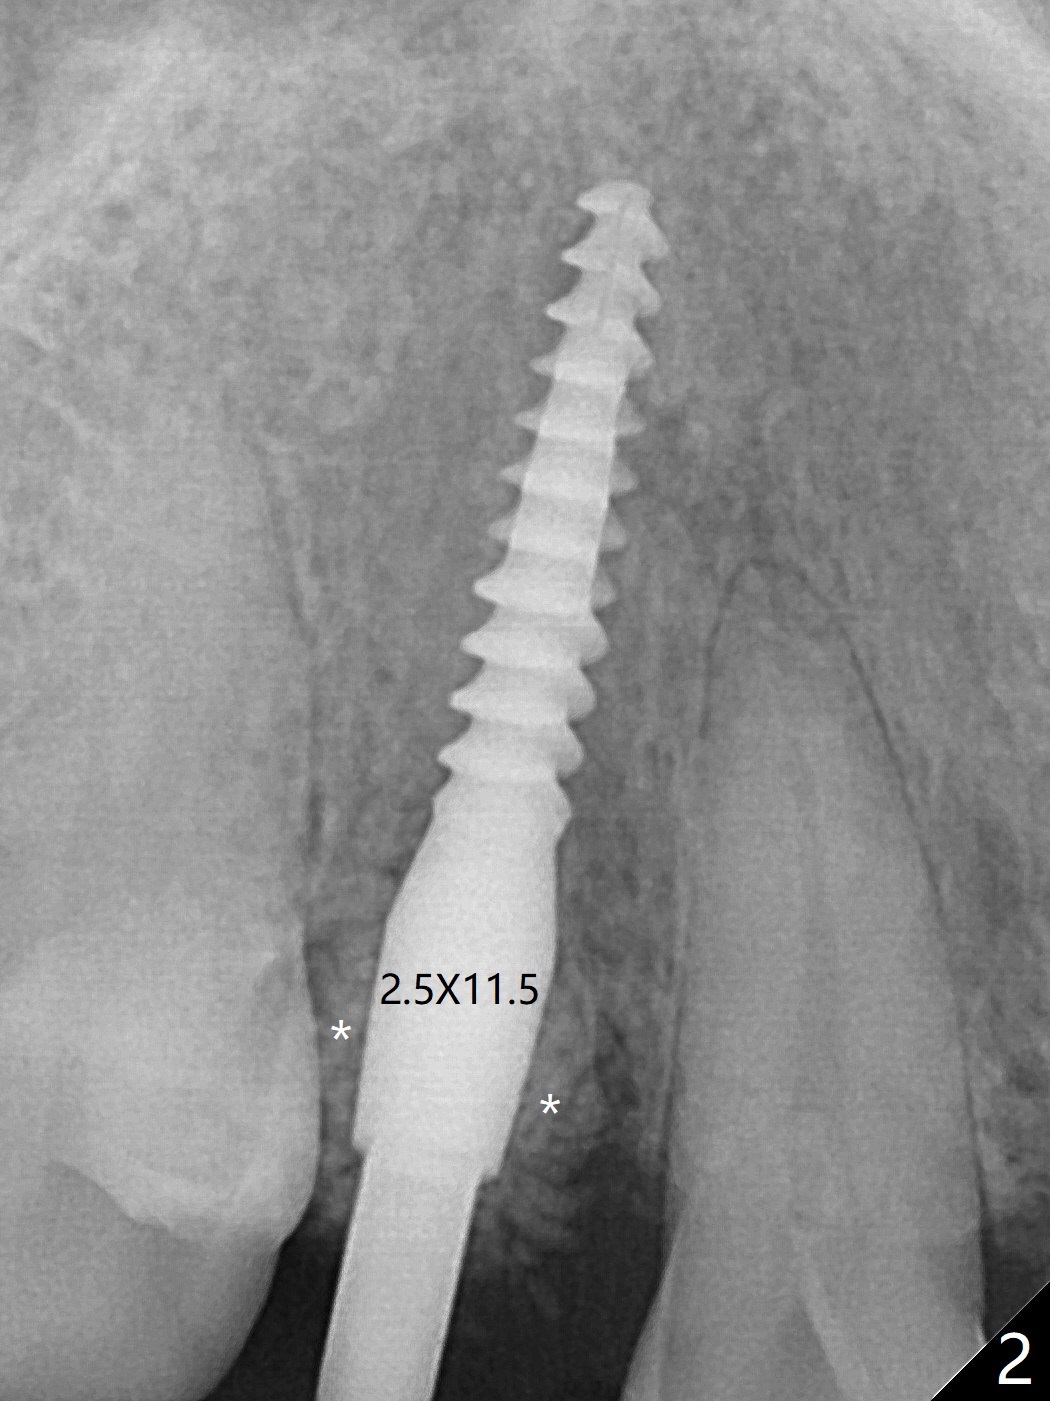

右上乳尖牙拔除后,颊侧尖牙隆起仍旧明显(图一:*(牙槽窝塞入止血纱布)),希望通过导板即种和植入粘性骨粉(图二:*)以及即修,这个局部解剖结构能保留下来。至少术后9天是这样(图三,T: 临时牙冠)。Return to Protect Graft Xin Wei, DDS, PhD, MS 1st edition 05/27/2021, last revision 06/05/2021